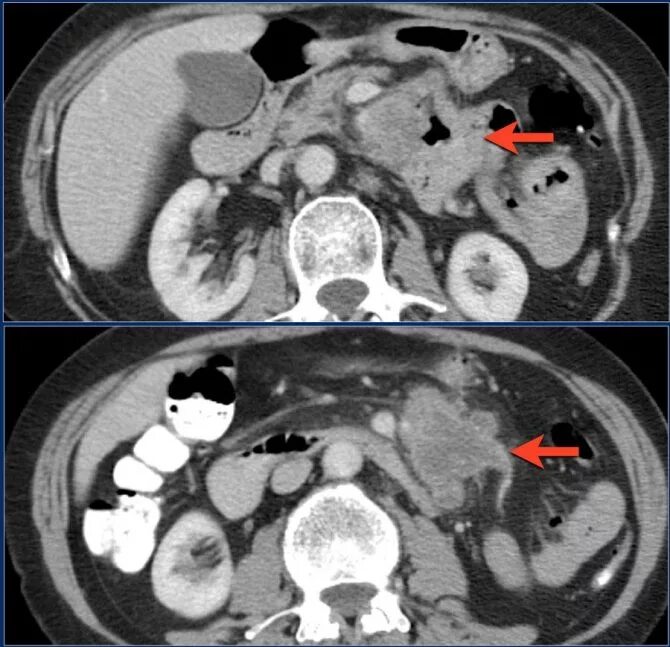

Метастазы при раке сигмовидной кишки